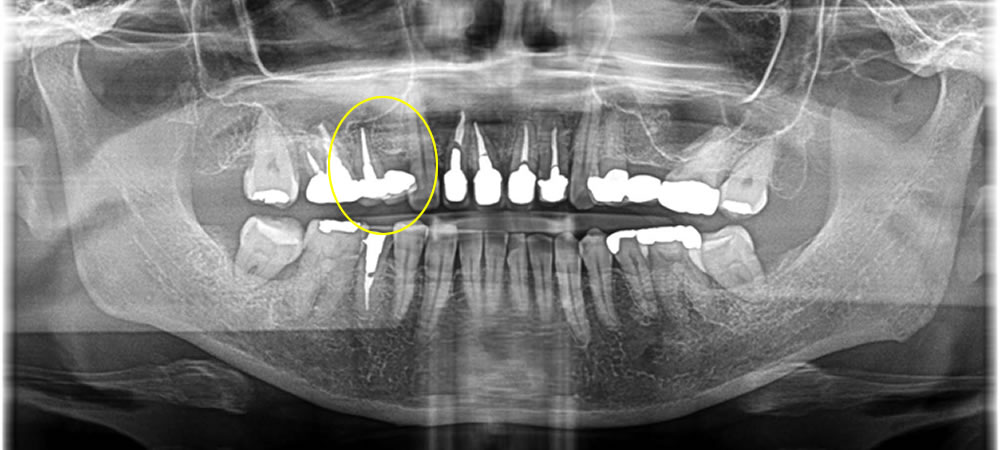

破折歯を抜歯してインプラントで治療した症例

年齢

40代

性別

男性

症例を見る